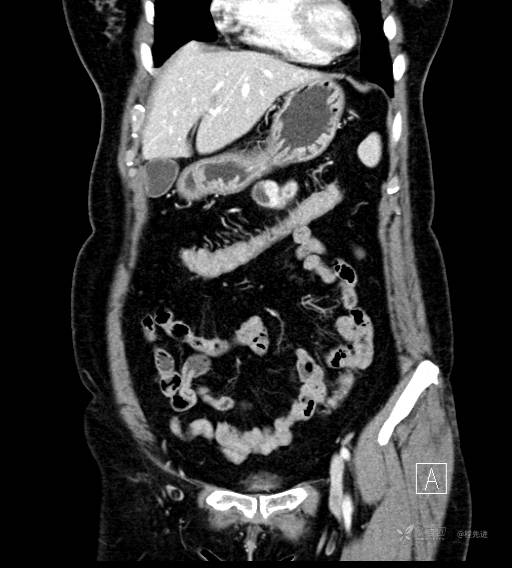

CT平扫